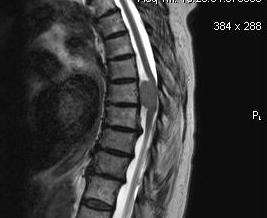

Osteoblastoma Spine0001Osteoblastoma Spine0002Osteoblastoma Spine0003